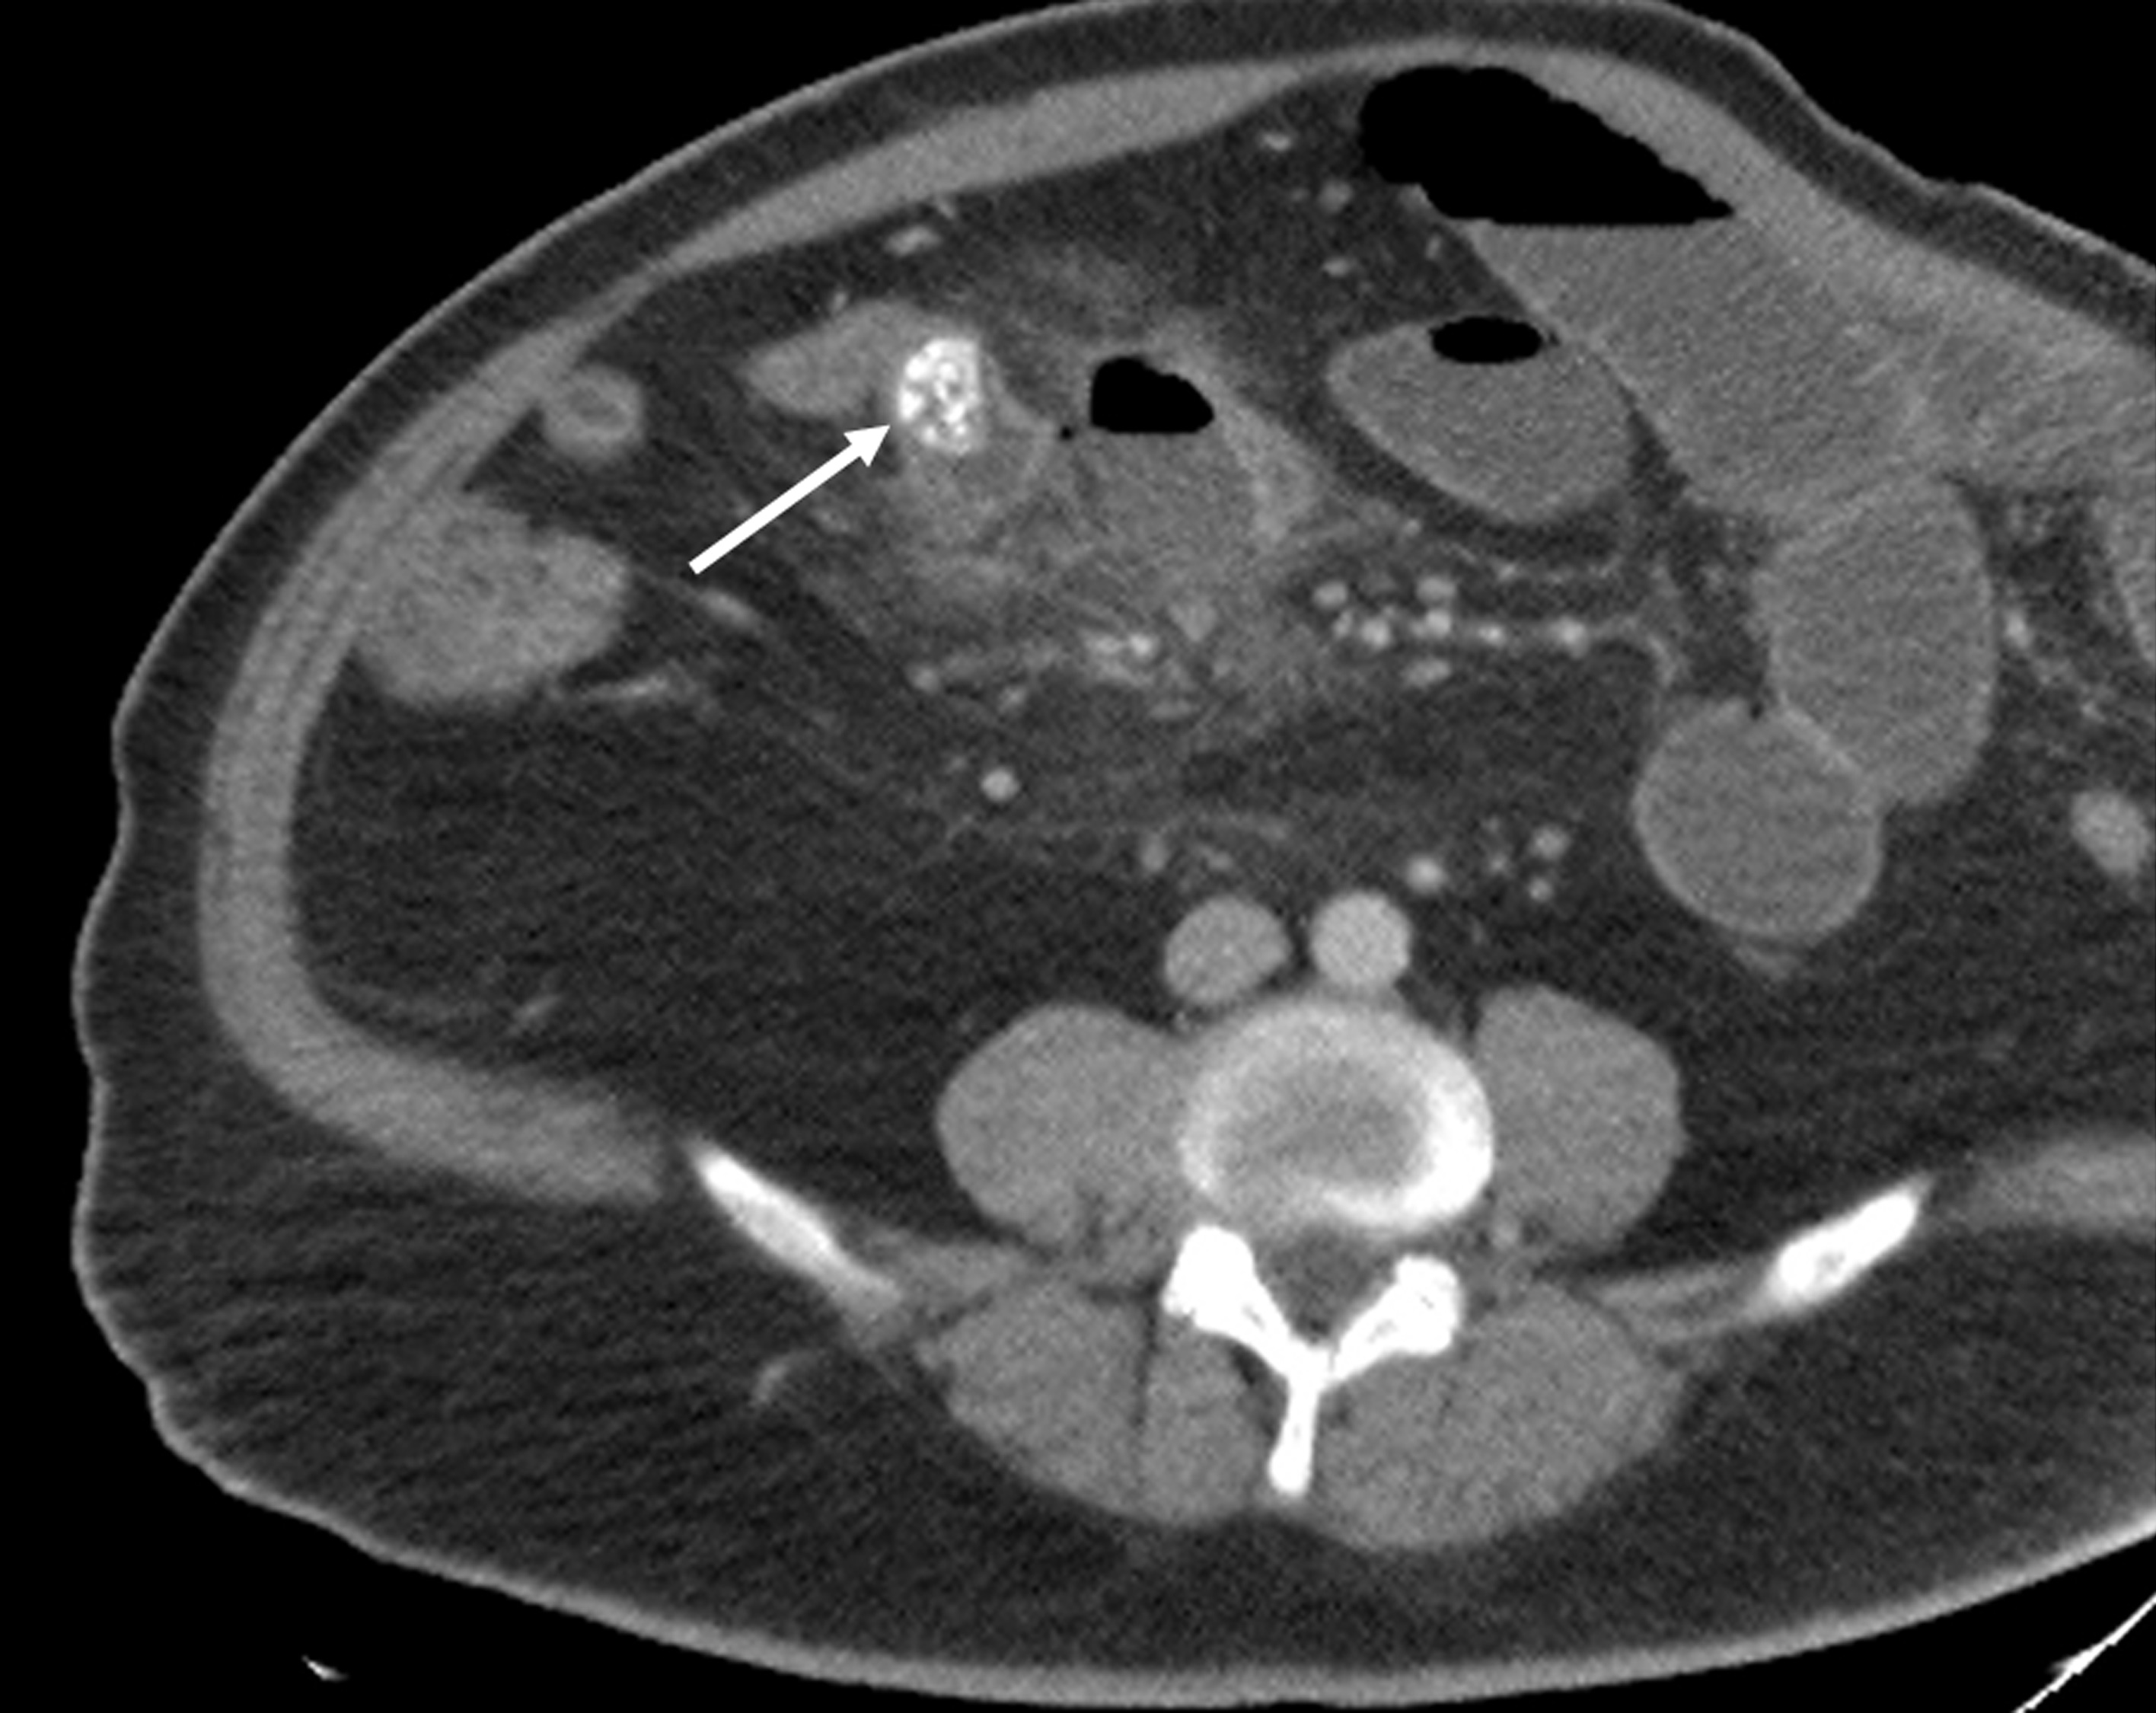

El divertículo de Meckel es la anomalía congénita más frecuente del tracto gastrointestinal, es un divertículo verdadero, ya que contiene todas las capas de la pared intestinal. Suele ser asintomático o se detecta de manera incidental en las pruebas de imágenes diagnósticas. Tiene un riesgo de complicación del 2-40%, siendo la más frecuentes la hemorragia, la obstrucción intestinal y la diverticulitis.

Se describe el caso de un paciente masculino de 52 años de edad, que consultó al servicio de urgencias del Hospital Universitario de Salamanca (España) por un cuadro de dolor abdominal, clínica infecciosa y  de obstrucción intestinal.

Mediante pruebas de imagen se diagnosticó una obstrucción intestinal secundaria a diverticulitis de Meckel por un enterolito, se realizó intervención quirúrgica y se confirmaron los hallazgos radiológicos descritos.